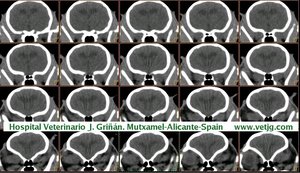

imágenes de TC en el gato | |||||||||||

Tomografía computarizada helicoidal |